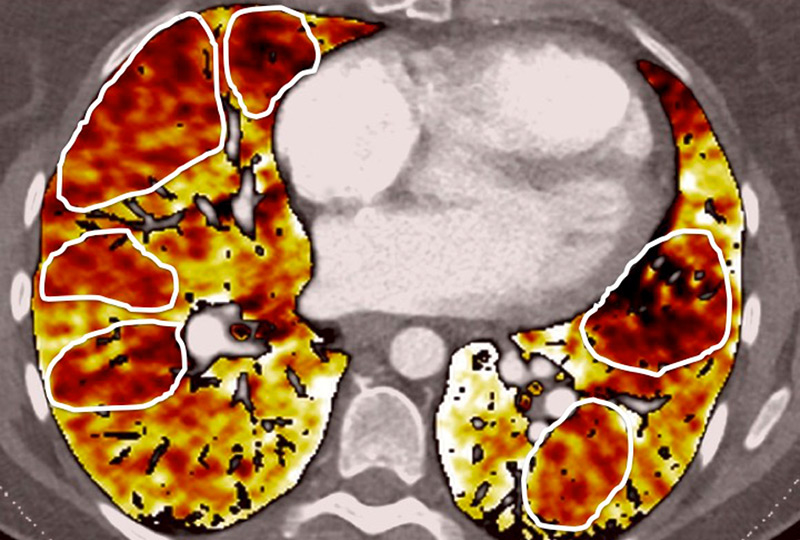

Nowadays, DECT imaging can be used for pathologies other than CTEPH and seems to offer advantages for PH characterisation because different DECT findings have been described in acute pulmonary embolism, CTEPH and idiopathic PAH (IPAH). In fact, perfusion defects are smaller and less defined in PAH than in CTEPH. This is likely due to focal under- and overperfusion as a result of the structural pulmonary vascular changes that occur in PH, which include vascular endothelial damage, cellular proliferation and occlusion in the distal pulmonary vasculature. Perfusion heterogeneities in DECT imaging are also common and seen in most cases of PAH. Findings of perfusion inhomogeneities related PAH have long been recognised in scintigraphy, and often are referred to as having a “mottled” pattern [42]. These perfusion defects are different from those seen in CTEPH, with nonsegmental and poorly defined defects (fig. 5). This heterogeneity is related to the severity of the disease. In PAH, this perfusion variability on scintigraphy is well correlated with pulmonary vascular resistance, as Talwar et al. showed [43]. Recently, similar results were published for DECT techniques (fig. 6). Ameli-Renani et al. described an increased enhancement of pulmonary arteries with reduced iodine lung perfusion in PH, and a good correlation of DECT perfusion heterogeneities with pulmonary vascular resistance; they showed a greater heterogeneity in parenchymal iodine maps in PH without pulmonary embolism [13]. The authors concluded that perfusion heterogeneities seen in DECT appear to be a direct reflection of pulmonary vascular resistance.

Figure 6

Perfusion heterogeneities in idiopathic pulmonary artery hypertension (stars) in two different patients (A/B). The dilatation of the arteries in pulmonary hypertension (arrows) is not always observed depending on the severity of pulmonary hypertension.